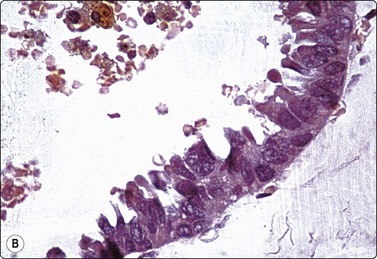

Fig. 7.13 Oxyphil/apocrine cells in cyst fluids

(A) Typical sheet of oxyphil cells with abundant cytoplasm and enlarged but bland nuclei (MGG, HP); (B) Sheet of oxyphil epithelium showing prominent nuclear enlargement, anisokaryosis, irregular chromatin and nucleoli, aspirated from simple benign cyst (Pap, HP).